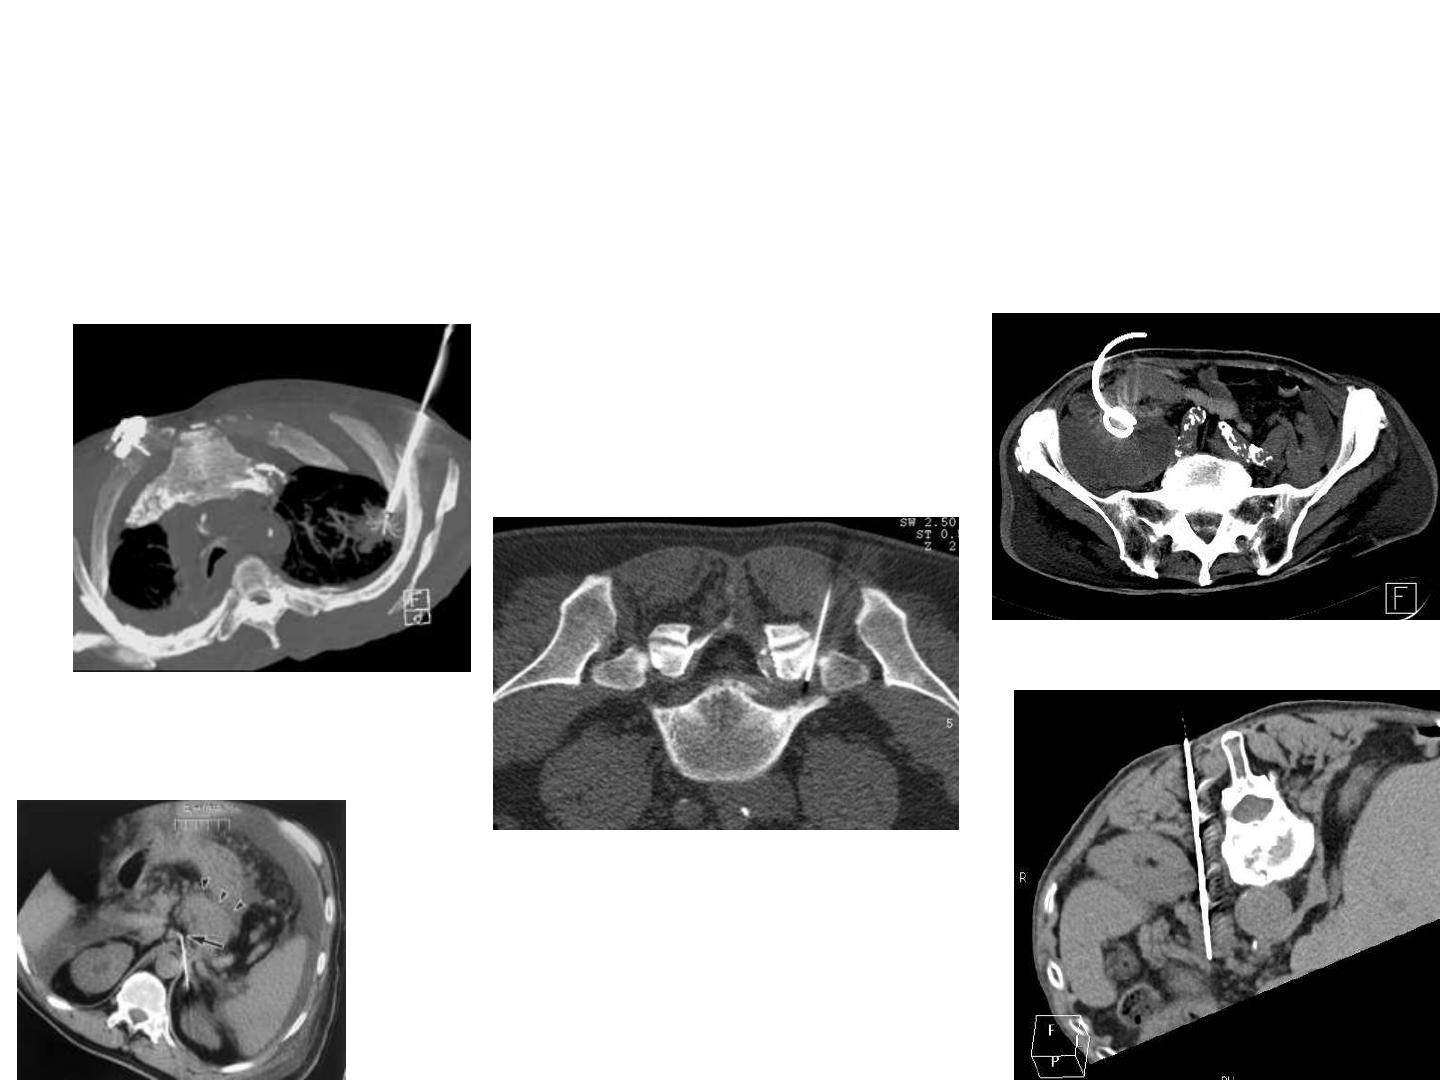

Cas clinique

Patient porteur

d’un syndrome

de Gilles de la

Tourette

mouvements

spastiques